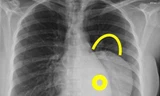

Qua hội chẩn, Bệnh viện đa khoa Đồng Nai nhận thấy khối u trong bụng đã chèn ép các mạch máu khiến hai cẳng chân dưới bị nhiễm trùng, làm mủ và sưng lên và chỉ định mỗ. Cuộc phẩu thuật được tiến hành lúc 13 giờ ngày 8/3 và đã thành công sau 3 tiếng, các bác sỹ đã cắt bỏ khối u nặng 13 ký (gồm 11 ký mô cứng và 2 ký dịch vàng).

Theo bệnh viện Đồng Nai khối u của bệnh nhân chiếm toàn bộ ổ bụng, che hết nội tạng. Hiện bệnh nhân đã tỉnh táo.